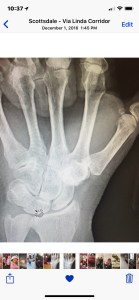

This X-ray shows the arthritis over two of the carpals in my wrist. It is considered a 4.5/5 on the rating scale. You should be able to see a couple of bones there, instead you see what looks like a cotton ball.